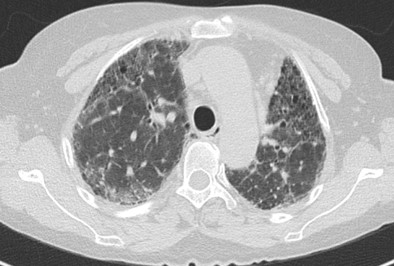

病例1:患者,男,60歲,因“咳嗽、活動(dòng)后氣促7個(gè)月”于2024年7月25日求診我院?;颊咴?個(gè)月內(nèi)先后4次就診其他醫(yī)院住院治療,均被診斷為“肺炎”,但治療后癥狀沒有改善,氣促反而加重。轉(zhuǎn)診我院后,間質(zhì)肺規(guī)范化診療中心主任張宏英經(jīng)詢問病史,患者從事木頭加工,考慮電鋸木粉吸入導(dǎo)致過敏性肺炎,經(jīng)影像科、病理科等多學(xué)科協(xié)助,最終確定了診斷:木屑所致的非纖維化型過敏性肺炎,治療不到1周,恢復(fù)出院。

病例5:患者,男,58歲,因“體檢發(fā)現(xiàn)肺部陰影20天”于2024年6月26日求診我院。既往接觸木屑、油漆,每1-2個(gè)月染頭發(fā)1次。

過敏原無處不在,但又很隱匿,宿主的易感性也不一樣。過敏性肺炎早發(fā)現(xiàn)、脫離環(huán)境就可以治愈,但是由于患者經(jīng)常未及時(shí)發(fā)現(xiàn)過敏原,對(duì)于早期肺部比較典型的影像特征也缺乏足夠的敏感性,仍繼續(xù)暴露在過敏環(huán)境中,最后發(fā)展成纖維化型過敏性肺炎。我院間質(zhì)肺規(guī)范化診療中心將盡可能詳盡地采集病史以發(fā)現(xiàn)可能存在的環(huán)境暴露因素以及時(shí)間軸關(guān)系,發(fā)揮多學(xué)科診療優(yōu)勢(shì),早發(fā)現(xiàn)早診斷,助力患者盡快脫離過敏原,避免不可逆的肺纖維化。